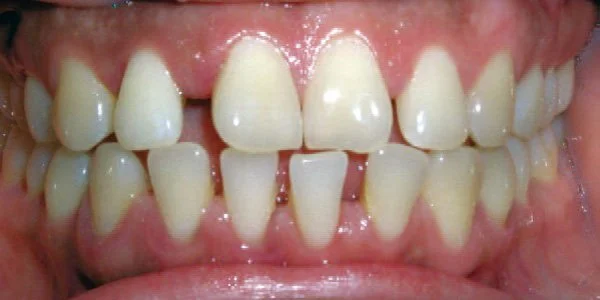

Spacing

Gaps between teeth